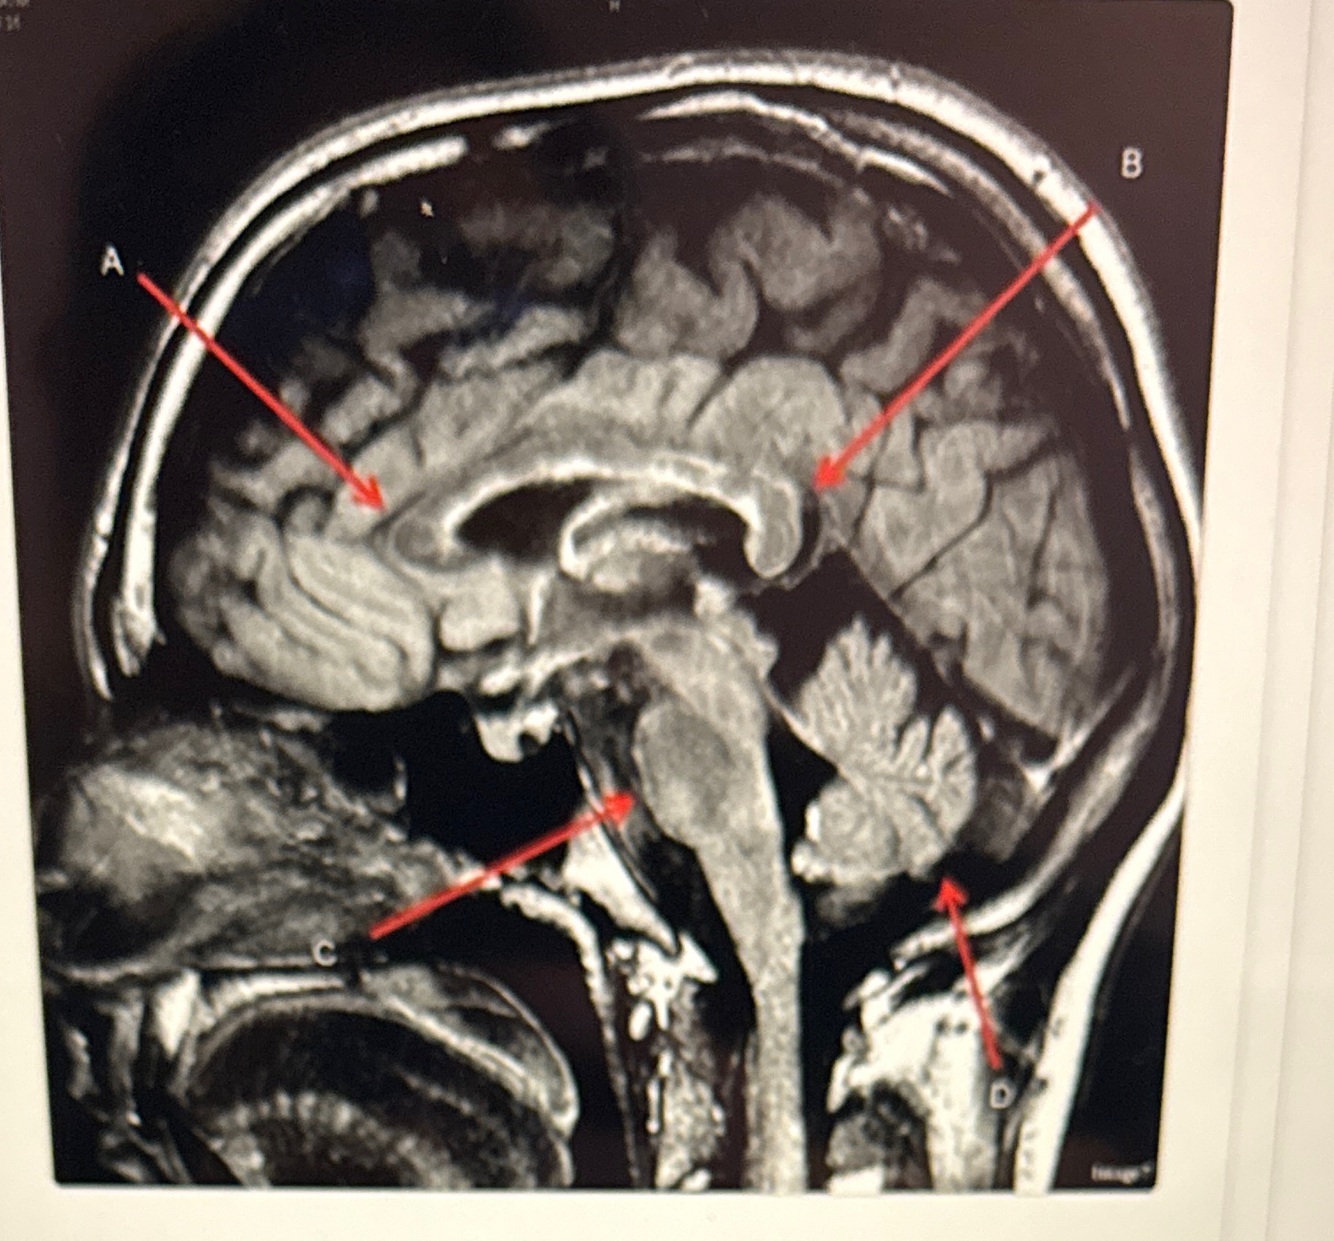

Letter A is pointing to

A

Genu of the corpus callosum

Letter E is pointing to

FORNIX

Q

Letter C is pointing to